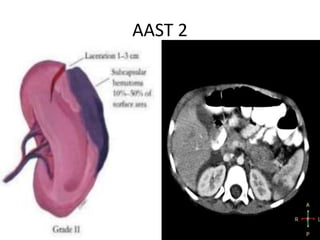

AAST Grading:

AAST 2